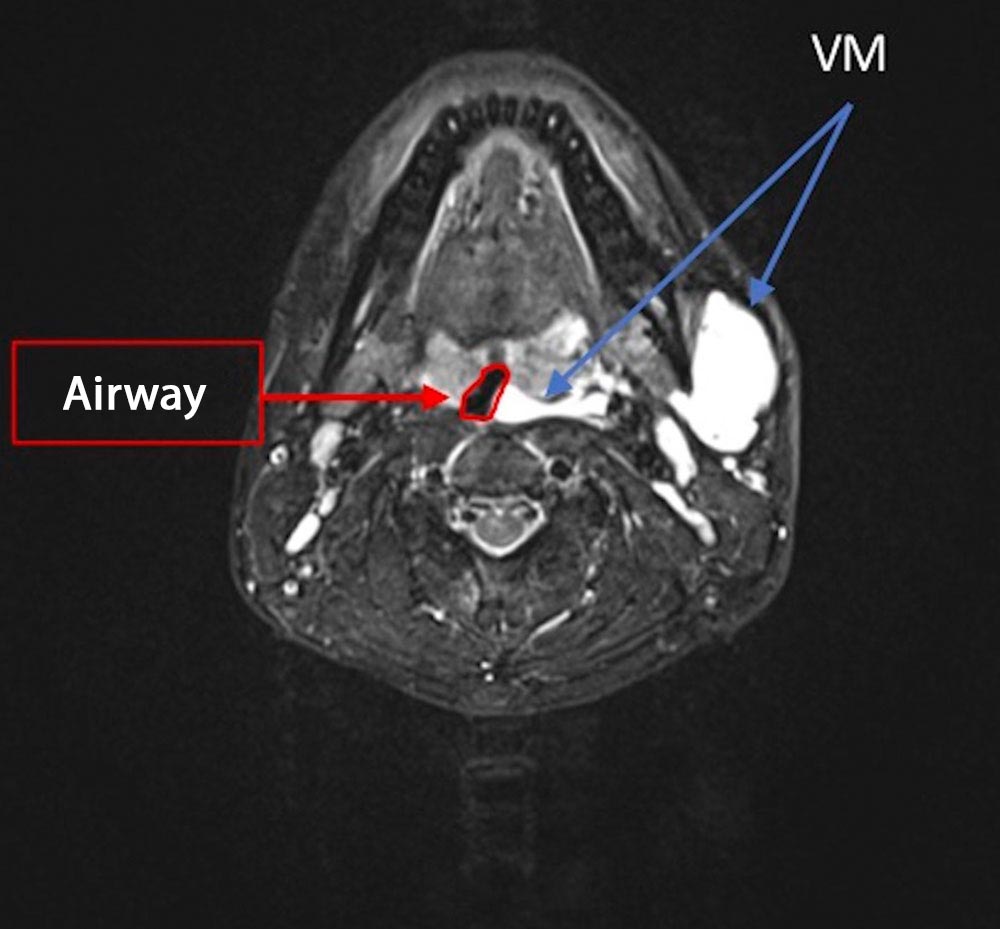

• Male patient aged 24 years.

• There is a voluminous venous malformation in the neck.

• The malformation extends into the piriform sinus and the glottic plane (hypopharynx).